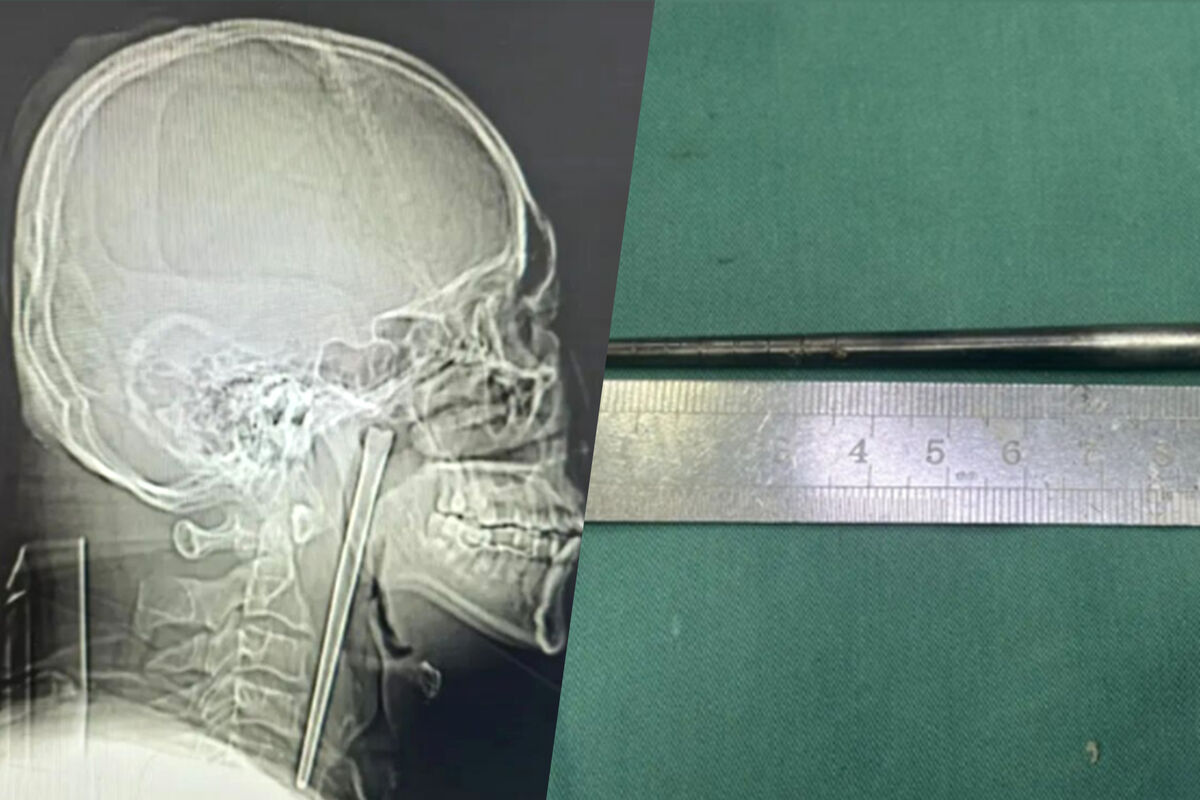

В китайском городе Далянь 46-летнего мужчину срочно доставили в больницу с сильной болью в горле. Во время обследования врачи нашли в его горле металлическую палочку длиной около 12 сантиметров, с которой пациент прожил восемь лет, пишет Mothership.

Обследование показало, что металлическая палочка застряла в задней части горла, при этом около трех сантиметров предмета выступали вверх. Несмотря на длительное пребывание инородного тела, врачи не обнаружили значительных кровотечений или язв.

Медики провели минимально инвазивную операцию и смогли извлечь палочку через рот, не прибегая к разрезу шеи.